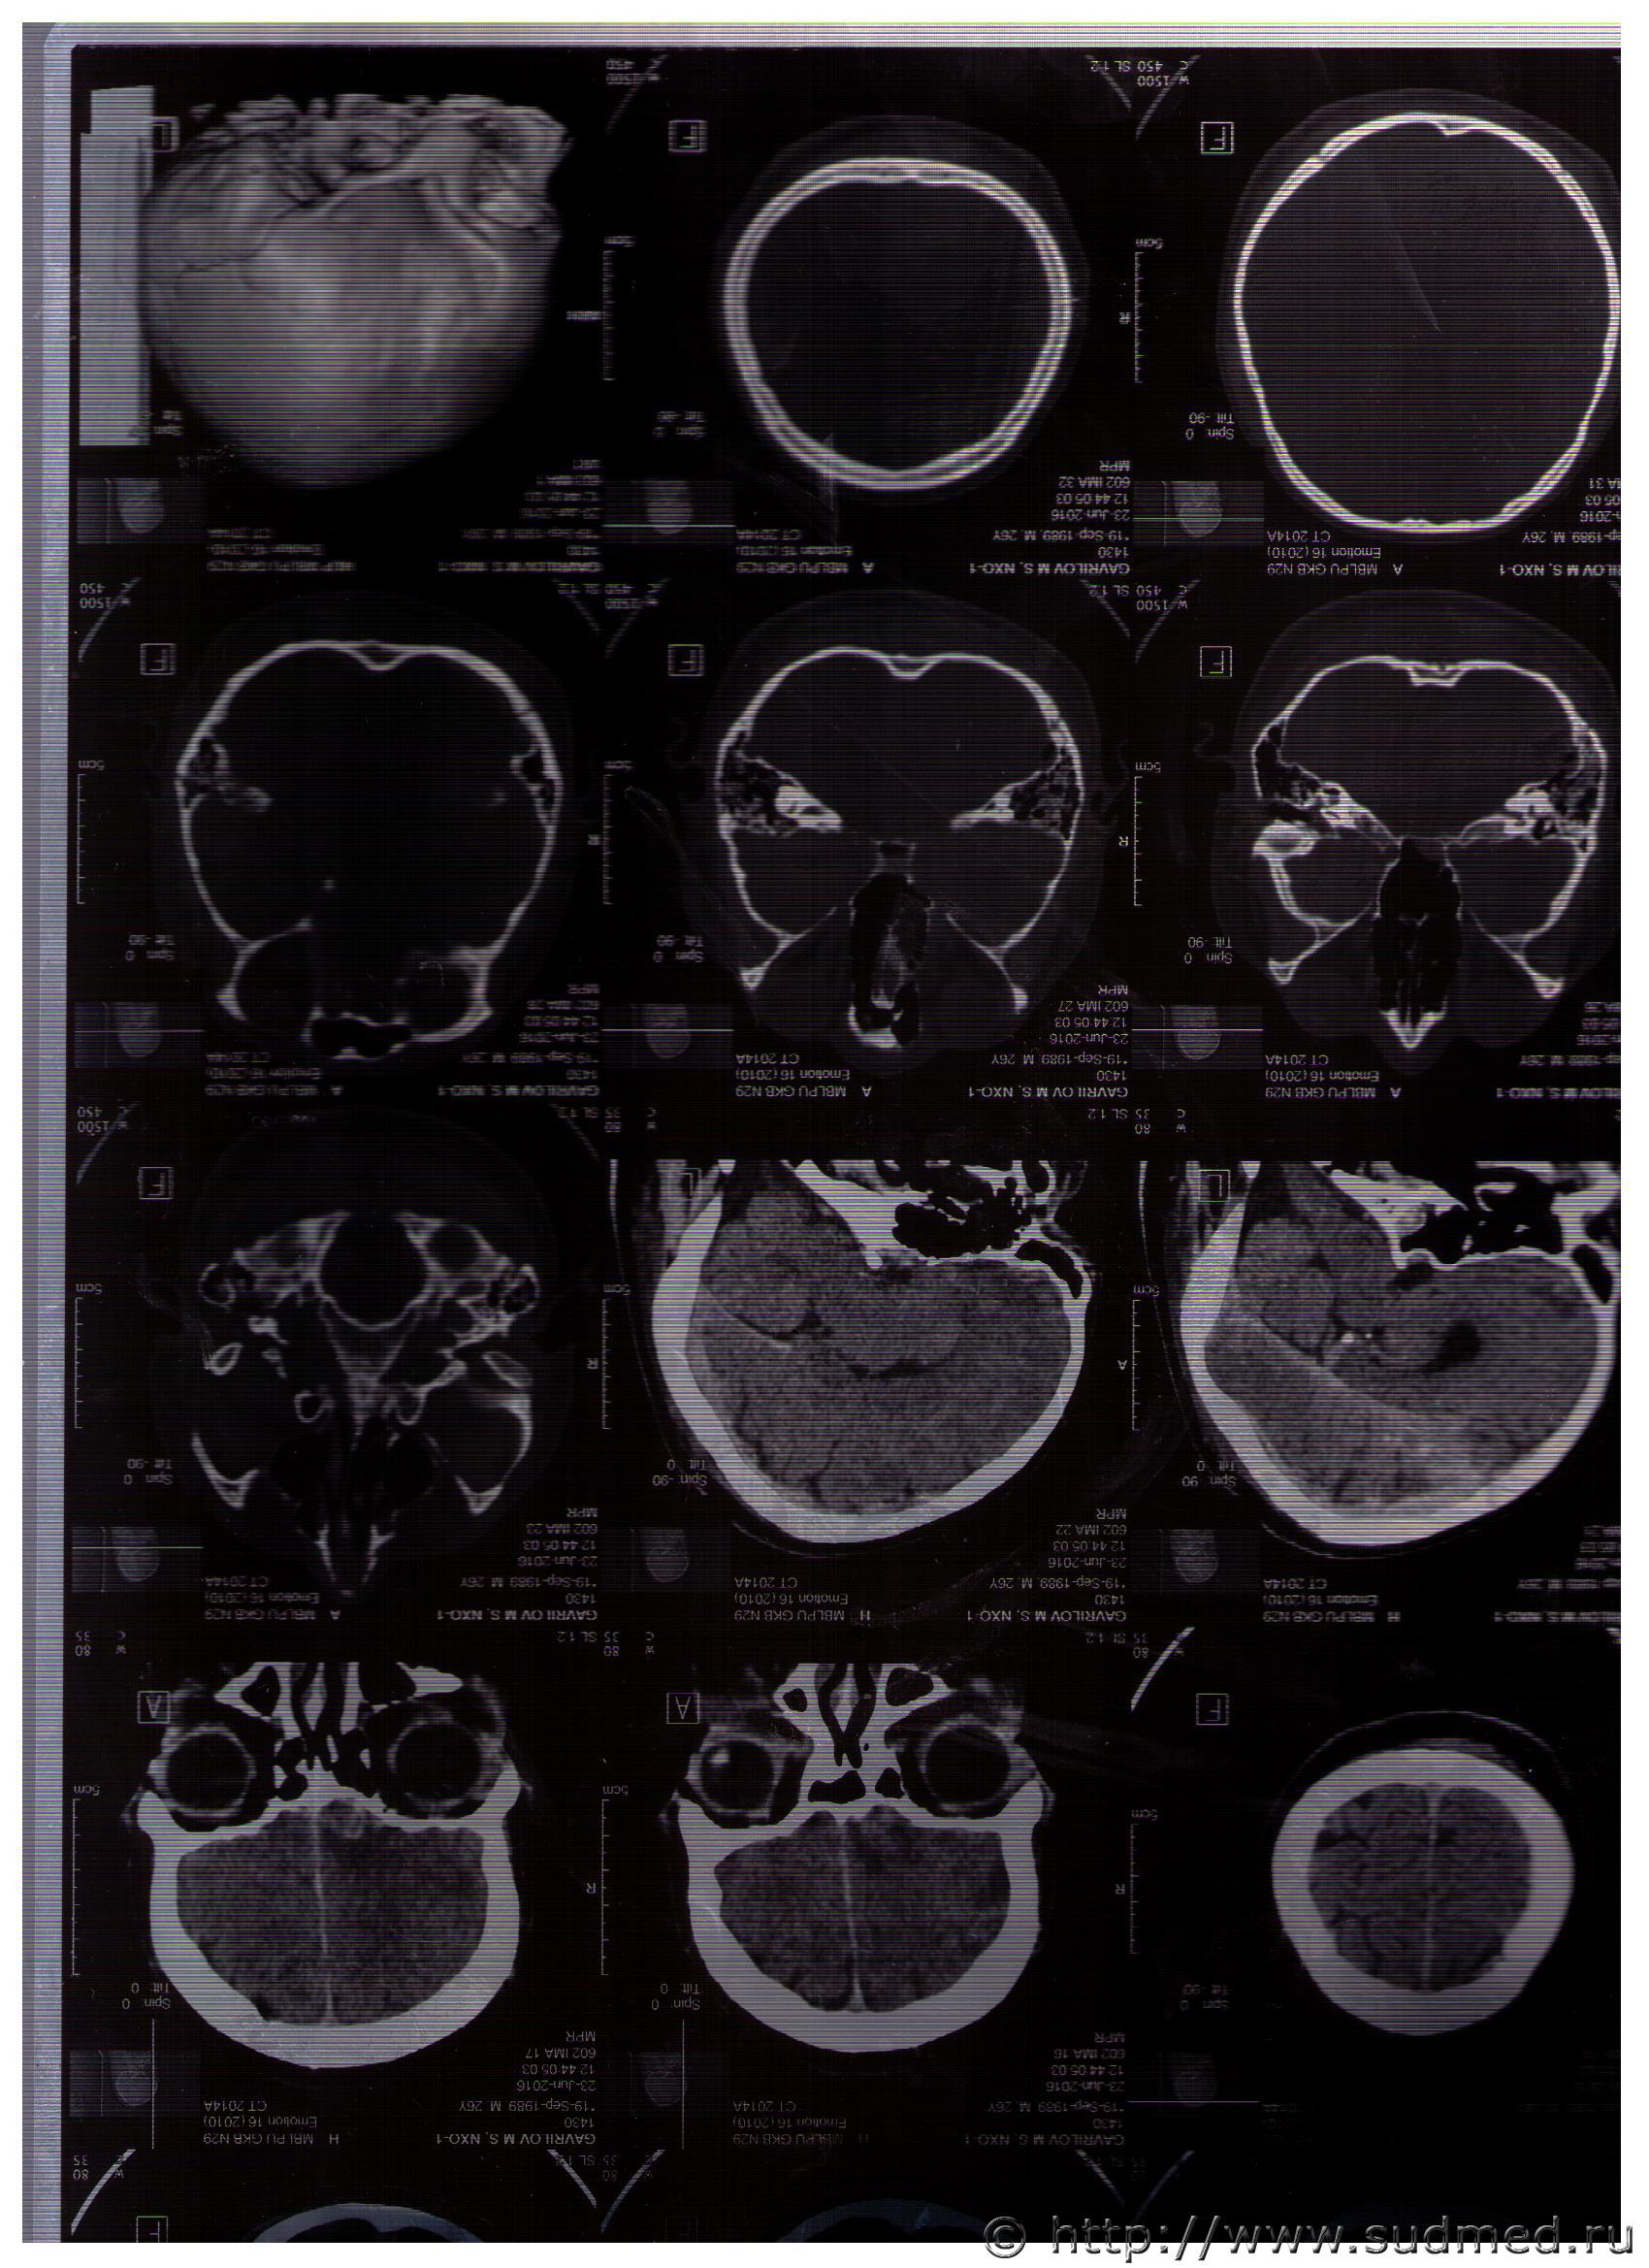

Судебная медицина - Прикрепленное изображение

Описание соответствует тяжкому вреду здоровья. Осталось все это эксперту увидеть воочию.

Сомнение в том, что расхождение черепных швов, как правило, продолжение локальных переломов, а не наоборот.